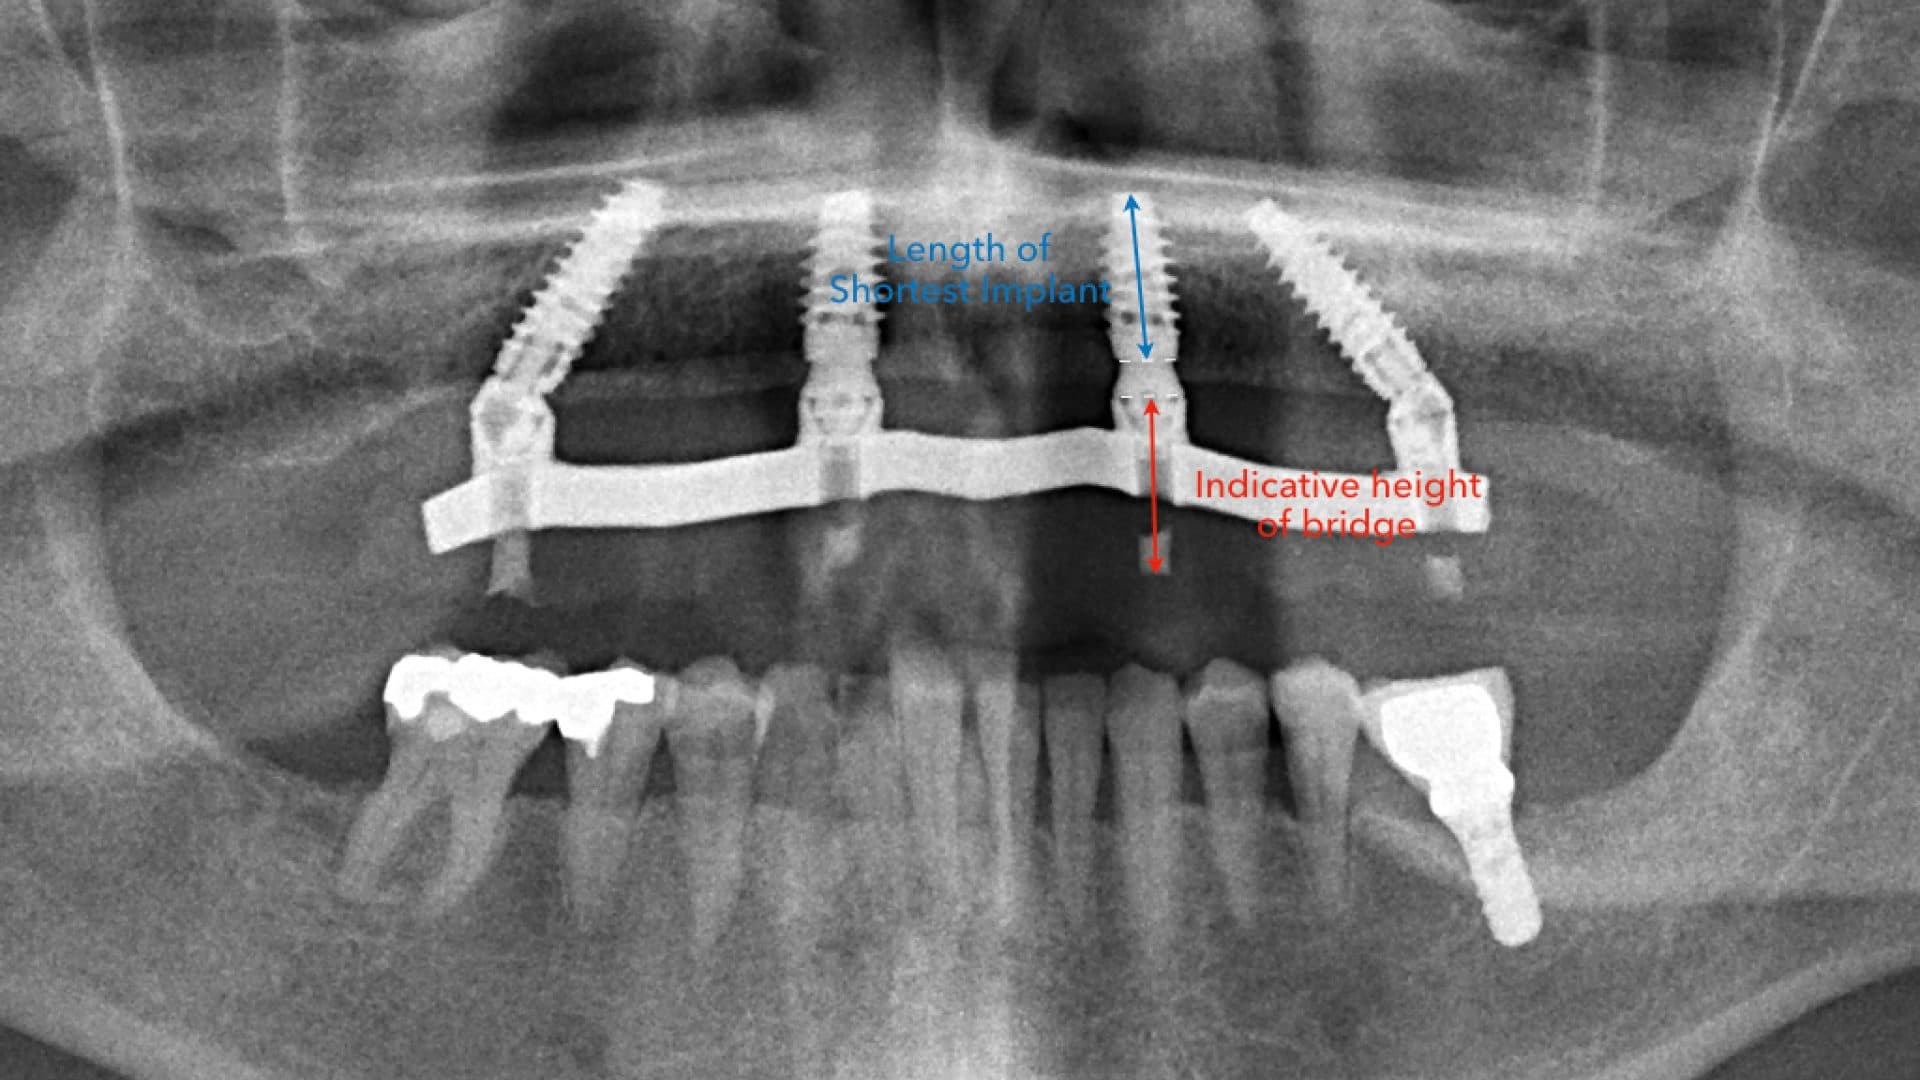

iii. Alignment on x-rays: there should be even spread, rigid connection between the implants, good bone levels, and the height of the prosthesis should be at least as tall as the shortest fixture (See pictures).

Ideal Situation